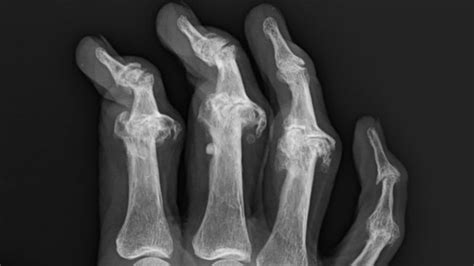

First things first, let’s chat about why our skin can be so tricky when we have PsA. Psoriatic arthritis is an autoimmune disease, meaning your immune system gets a little confused and starts attacking healthy tissues – both in your joints and on your skin. This is what causes psoriasis, the skin condition that often goes hand-in-hand with PsA. Those red, scaly patches? Yeah, that’s psoriasis in action. But it doesn’t stop there. PsA can also lead to dry, flaky skin, increased sensitivity, redness, and even itching. It’s a whole package, right? Skincare for psoriatic arthritis isn’t just about looking good; it’s about feeling comfortable in your own skin and managing flare-ups. When your skin is inflamed or irritated, the last thing you want is a harsh cleanser or a makeup product loaded with potential irritants. Think of it as giving your skin some extra TLC, especially when your body is already working overtime fighting inflammation. We need products that soothe, moisturize, and protect without triggering that dreaded sensitivity. It’s a delicate balance, for sure, but totally achievable with the right knowledge and products. And the good news is, more and more brands are recognizing this need, especially here in Germany, a country known for its high standards in dermatological care and quality products. So, understanding these skin challenges is the first step towards finding the best cosmetics for psoriatic arthritis in Germany.